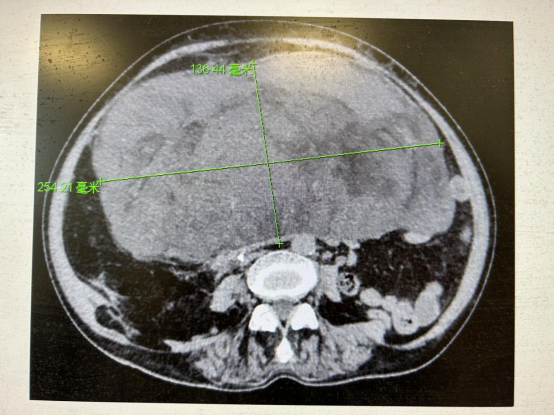

从增强CT的影像可清晰地看到老人的腹部后巨大肿瘤直径超过25公分,上达剑突、下达子宫,上极压至肝门部,压迫下腔静脉和滤器,右侧压迫右输尿管,且肿瘤最右侧将盲肠、回肠推至肝区,下极压迫膀胱与子宫粘连,其余压迫结肠、胃等器官。